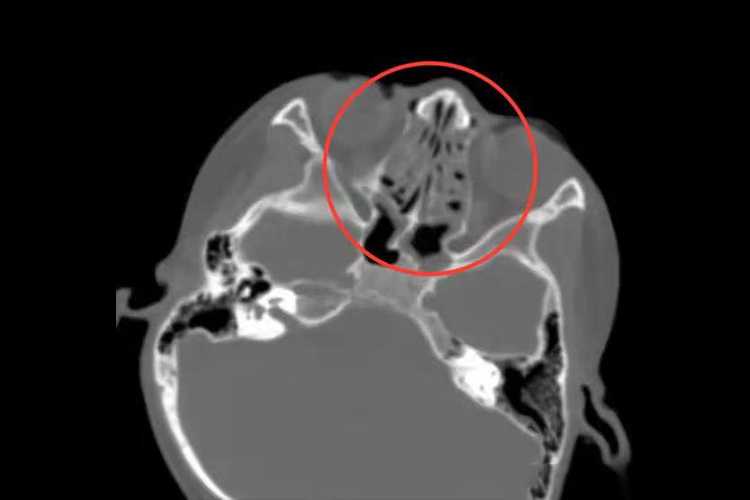

慢性肥厚性鼻炎:慢性肥厚性鼻炎患者发病时,CT检查可见鼻腔黏膜增生、肥厚,下鼻甲肿大,骨质增生,鼻腔狭窄,部分患者可伴有鼻腔结构异常。

变应性鼻炎:变应性鼻炎患者发病时,CT检查可见鼻甲肥大,窦腔黏膜肥厚,鼻腔通气截面积缩小,鼻腔鼻窦可有少量积液。